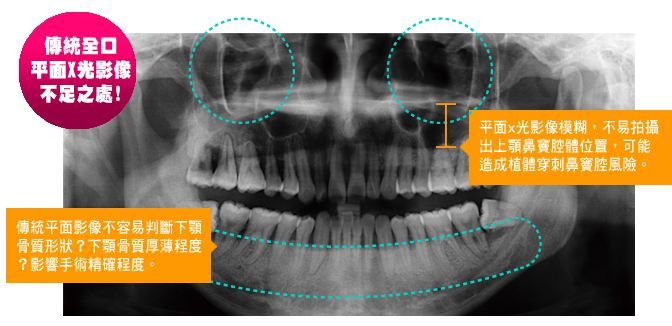

如果只靠傳統的口內x光或全景x光攝影,僅能提供片面的影像資訊,冒然進行植牙等治療,手術風險相對提高!

口腔內,上、下顎齒槽骨有著複雜的解剖型態,其中主要的下顎神經管隱藏於骨頭深處,上顎則有鼻竇腔室埋藏其中。

若在植牙手術前,沒有經過精密的電腦斷層掃描攝影診斷、手術評估,因為診斷資料不足夠,而相對造成手術風險提高,有可能傷及下顎神經管,進而造成顏面神經的永久傷害,或者植牙定位不精準,穿透上顎骨質,破壞鼻竇腔室…等醫療風險。

每一個人的齒槽骨解剖形狀不全然相同,骨頭厚薄、神經走向分布也不會完全一樣,利用牙科電腦斷層掃描攝影,精確重建了每個就診患者的口腔骨頭、神經3D型態分布,提供醫師精密手術時的必要幫助。相對的,若以傳統口內x光攝影,僅能拍攝出上下顎骨頭、牙齒某個角度的片面影像,對於神經走向定位、鼻竇空間位置的影像判斷不夠精確。